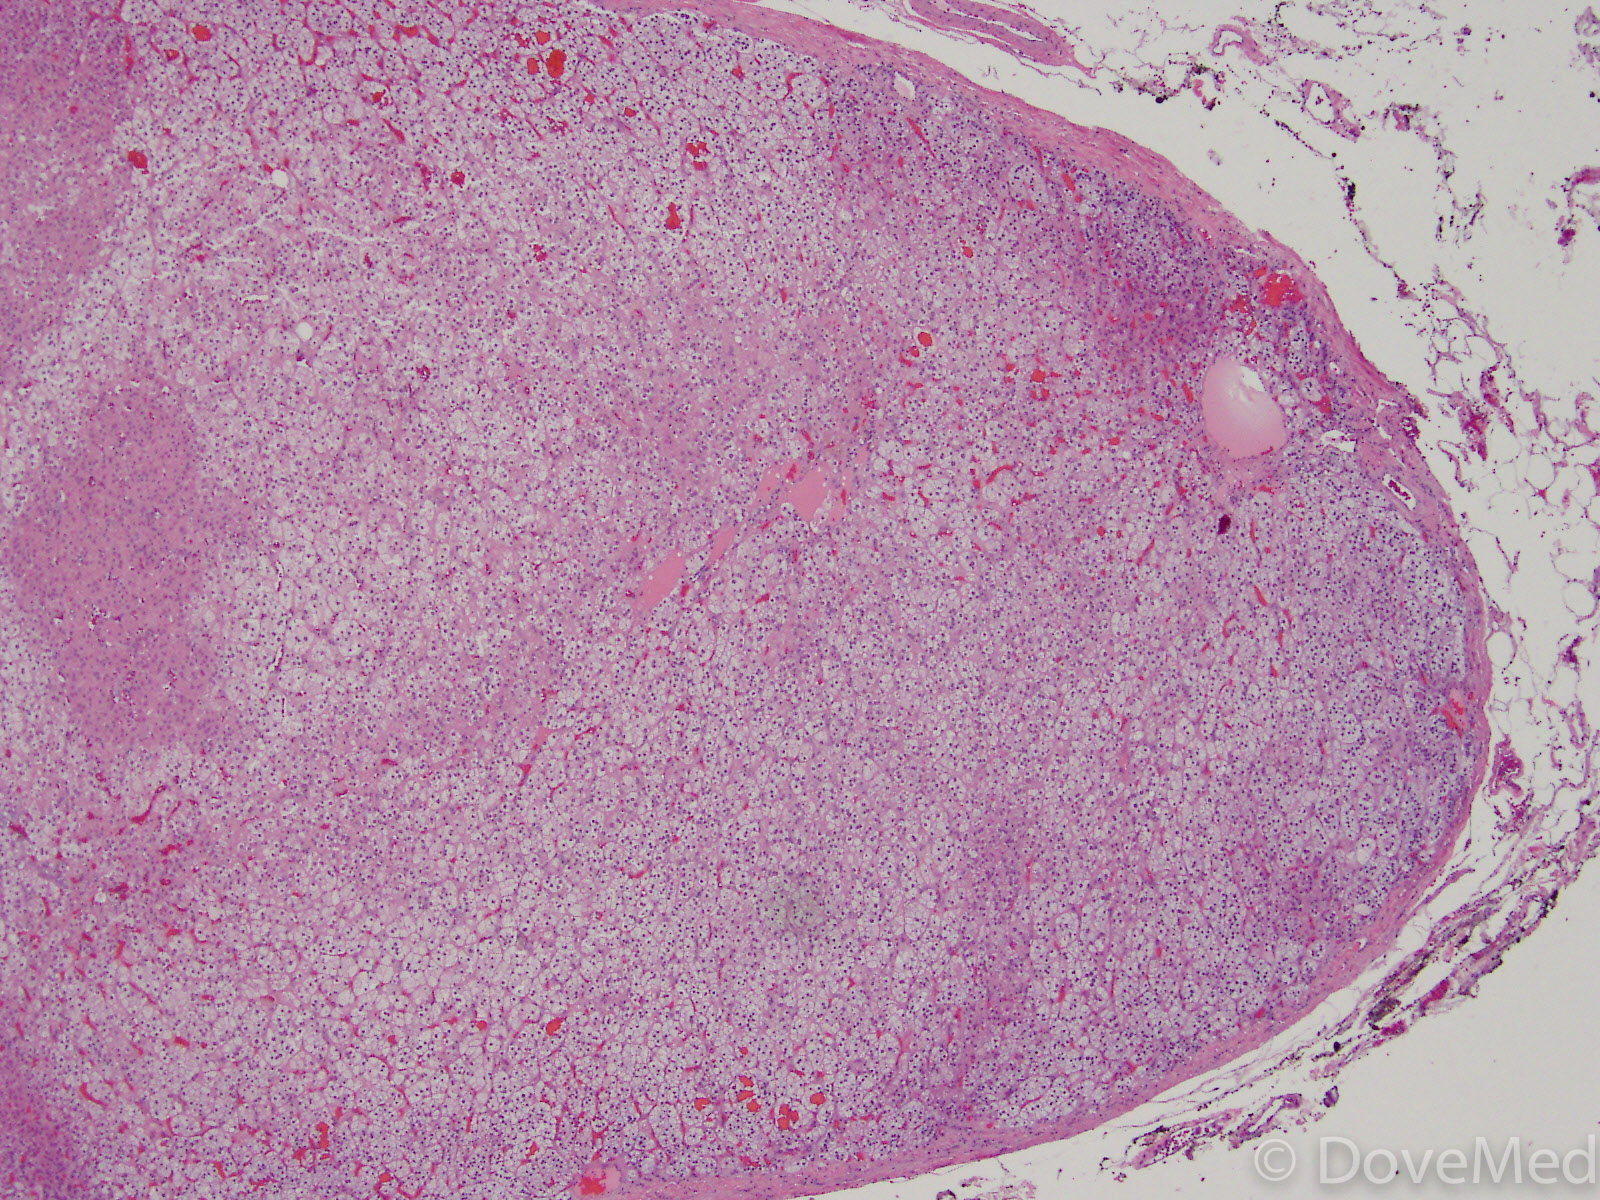

From www.dovemed.com

Adrenal Gland Needle Biopsy What Is Biopsy Adrenal Gland A sample of tissue is taken from. They make hormones that help control important. Your adrenal glands are glands that sit on top of your kidneys, under your ribs. A needle biopsy of the adrenal gland is a procedure to take a tiny sample of your adrenal gland tissue. An adrenal gland biopsy is a procedure used to check for. What Is Biopsy Adrenal Gland.